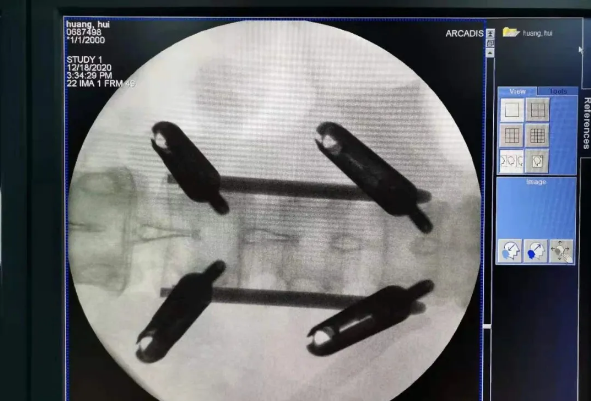

患者為22歲年輕女性,因車禍致骨盆骨折。骨盆骨折是一種復(fù)雜的創(chuàng)傷,傳統(tǒng)手術(shù)方式需要比較大的切口,而且骨盆內(nèi)有大量復(fù)雜血管和神經(jīng),手術(shù)難度和風(fēng)險(xiǎn)極大,是很多骨科醫(yī)生的禁區(qū)。

在南昌市第一醫(yī)院廖琦教授帶領(lǐng)下,由創(chuàng)傷骨科團(tuán)隊(duì)借助天璣?骨科手術(shù)機(jī)器人為患者“量身定做”最理想、最安全的教科書般的通道,完美安全微創(chuàng)完成手術(shù),并且手術(shù)時(shí)間明顯縮短,真正做到“指哪兒打哪兒”!更讓患者放心的是,天璣?骨科手術(shù)機(jī)器人的“穩(wěn)定手”機(jī)械臂進(jìn)行精準(zhǔn)定位,不用反復(fù)探尋。

由于天璣?骨科手術(shù)機(jī)器人的精準(zhǔn)及高效,可以使手術(shù)時(shí)間明顯縮短,因此在骨盆骨折手術(shù)后,在廖琦教授指導(dǎo)下,脊柱外科團(tuán)隊(duì)利用天璣?骨科手術(shù)機(jī)器人同樣為20歲女性腰椎骨折患者“量身定做”最理想、最安全的教科書般的通道,完美安全微創(chuàng)完成手術(shù),手術(shù)不僅時(shí)間縮短,并且出血和透視減少。